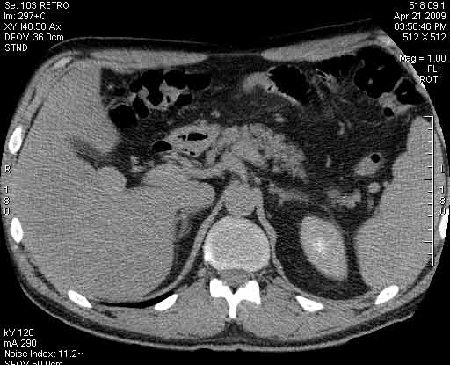

Сонограммы, КТ- артериальная, портальная и отсроченная паренхиматозная фазы

Сделали КТ (весьма похвальная тактика); по КТ: в артериальную фазу: периферическое усиление в виде сливающихся островков контраста, с центрипетальной направленностью. Венозная и отсроченная фаза-хорошее накопление контраста; образование практически изоденсно по отношению к паренхиме печени. Классика гемангиомы. Вуаля-диагноз на "тарелочке".